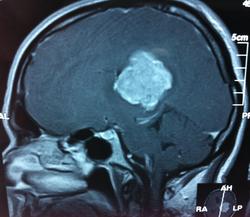

Начало вот здесь http://www.radiomed.ru/cases/kt-gms-obemnoe-obrazovanie-levoi-gemisfery-bolshogo-mozga-vnutrizheludochkovaya-meningioma. Пациент оперирован (меня сначала дезинформировали по поводу операции), перед операцией состояние ухудшилось, возникла правосторонняя гемиплегия, которая осталась и после декомпрессии. МРТ, КТ снимки и выписку предоставила супруга пациента, снимал на iphone, простите за качество, дисков с исследованиями не записывали. Надеюсь вопрос по данному случаю исчерпан.

Вот "цветочки":

T1+C

И Вы считаете, что эта опухоль имеет интравентрикулярную локализацию?

Изначально по КТ я так предпологал, а теперь на 100% уверен, разве МРТ это не показало? Гистологически - менингиома, опухоль мозговой оболочки. Покажите, пожалуйста, образование где-нибудь прилежит к костям, где есть мозговая оболочка? Я не вижу, зато отчетливо вижу в левом боковом желудочке из оболочек сосудистого сплетения. Что вас еще смущает? По-моему, предостаточно фактов, чтобы развеять все сомнения.

Мне видится так. Иначе в данной локализации просто неоткуда расти оболочечной опухоли. На контрольной КТ, после декомпрессии, когда срединные структуры стали действительно срединны, правое обызвествленное сосудистое сплетение видно отчетливо, а левое, где оно? Ведь если бы образование компремировало, то после операции, когда часть мозга пролабировало в трепанационное отверстие мы бы увидели и левое сосудистое сплетение, но оно интимно связано с образованием и даже "потянулось" за ним в сторону декомпрессионного отверстия, потому что это и есть "росток" откуда выросла опухоль.